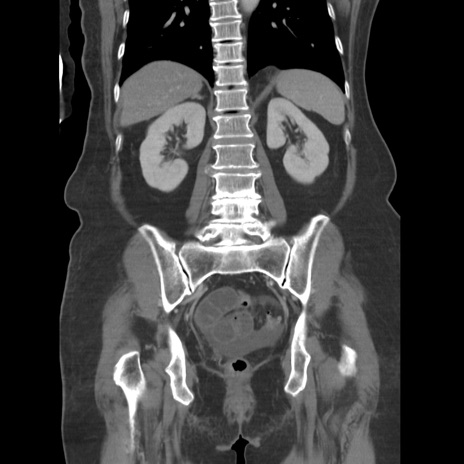

症例19(冠状断像)

【症例】80歳代女性

【主訴】下腹部痛

【現病歴】約8時間前より下腹部痛の出現あり、救急外来受診。

【既往歴】両側付属器切除

【身体所見】意識清明、下腹部正中に手術痕あり、その部位に一致して圧痛と反跳痛あり。腸蠕動音は亢進。

【データ】WBC 9300、CRP 0.15